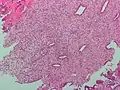

Micrographie d'endomètre décidualisé en raison de progestérone exogène. Coloration HE.